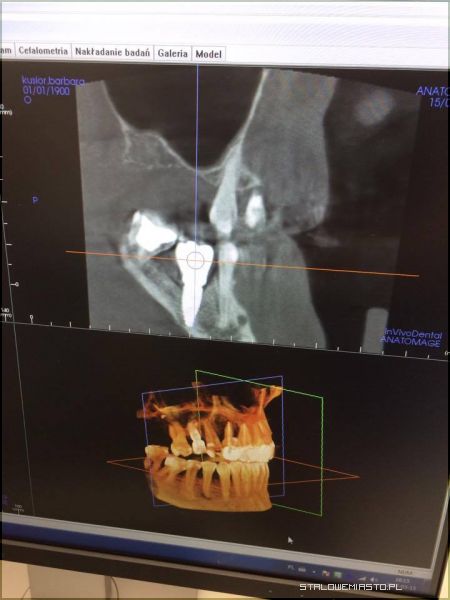

Świat zaczyna się w Stalowej WoliStomatolog Piotr Trafidło znany jest z tego, że w swojej pracy posługuje się urządzeniami i materiałami z najwyższej półki. Nie dziwi więc fakt, że w Centrum Precyzyjnej Stomatologii Multident pojawił się właśnie supernowoczesny sprzęt, na którym pracują stomatolodzy tylko w najlepszych klinikach Europy. Tego typu urządzenia w Polsce wciąż należą do rzadkości. Mowa tu o nowoczesnym tomografie umożliwiającym pozyskiwanie obrazów z rekonstrukcją 3D do aktualnie wykonywanych zabiegów. Aparat Gendex pozwala również na zmianę dawki promieniowania RTG, poprzez wykonywanie radiogramów dostosowanych do rozmiarów ciała. Jest więc bardzo bezpieczny dla pacjenta. Wykonuje zdjęcia najwyższej jakości. Dzięki niemu można precyzyjnie i szybko określić przyczynę dolegliwości, obejrzeć zęba w każdej płaszczyźnie, wykonać symulację komputerową i dotrzeć do źródła problemu bez eksperymentowania i przewidywania. Leczenie wówczas staje się tak precyzyjne, że nie ma tu możliwości popełnienia błędu przy stawianej diagnozie, a takie błędy mogą się zdarzyć, gdy korzysta się ze zwykłego aparatu RTG. Tomograf wyposażony jest również w cefalometrię co umożliwia bardzo dokładną diagnostykę wad ortodontycznych oraz zaplanowanie najlepszego leczenia ortodontycznego.

Bo diagnostyka jest najważniejszaW XXI wieku nie jest sztuką skorzystanie z pomocy stomatologa. Sztuką jest wybranie takiego gabinetu, gdzie nasze problemy zostaną rozwiązane kompleksowo, bezpiecznie, a przede wszystkim niezwykle dokładnie. Piotr Trafidło od wielu lat pracuje jako implantolog. W swojej karierze zawodowej ma na koncie blisko 2 tysiące udanych zabiegów implantologicznych. Jest „autorem” wielu uśmiechów na Podkarpaciu. Tomograf 3D pomoże mu w jeszcze lepszej diagnostyce, dzięki czemu możliwe będzie np. określenie grubości i gęstości kości, a co za tym idzie, dobranie najlepszego dla danego pacjenta implantu. Pojawienie się takiego urządzenia w Multident to rewolucja na rynku medycznym w regionie. Skuteczność leczenia będzie teraz tak duża, że firma może w ciemno zagwarantować, że w sytuacji gdyby implant jakimś cudem się nie przyjął, pacjent będzie mógł otrzymać stuprocentowy zwrot kosztów leczenia.